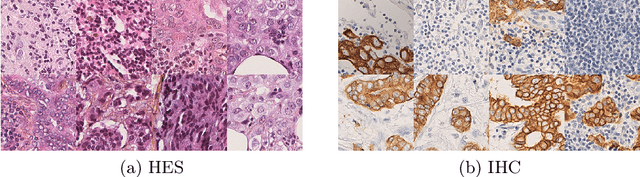

Abstract:In whole slide imaging, commonly used staining techniques based on hematoxylin and eosin (H&E) and immunohistochemistry (IHC) stains accentuate different aspects of the tissue landscape. In the case of detecting metastases, IHC provides a distinct readout that is readily interpretable by pathologists. IHC, however, is a more expensive approach and not available at all medical centers. Virtually generating IHC images from H&E using deep neural networks thus becomes an attractive alternative. Deep generative models such as CycleGANs learn a semantically-consistent mapping between two image domains, while emulating the textural properties of each domain. They are therefore a suitable choice for stain transfer applications. However, they remain fully unsupervised, and possess no mechanism for enforcing biological consistency in stain transfer. In this paper, we propose an extension to CycleGANs in the form of a region of interest discriminator. This allows the CycleGAN to learn from unpaired datasets where, in addition, there is a partial annotation of objects for which one wishes to enforce consistency. We present a use case on whole slide images, where an IHC stain provides an experimentally generated signal for metastatic cells. We demonstrate the superiority of our approach over prior art in stain transfer on histopathology tiles over two datasets. Our code and model are available at https://github.com/jcboyd/miccai2022-roigan.